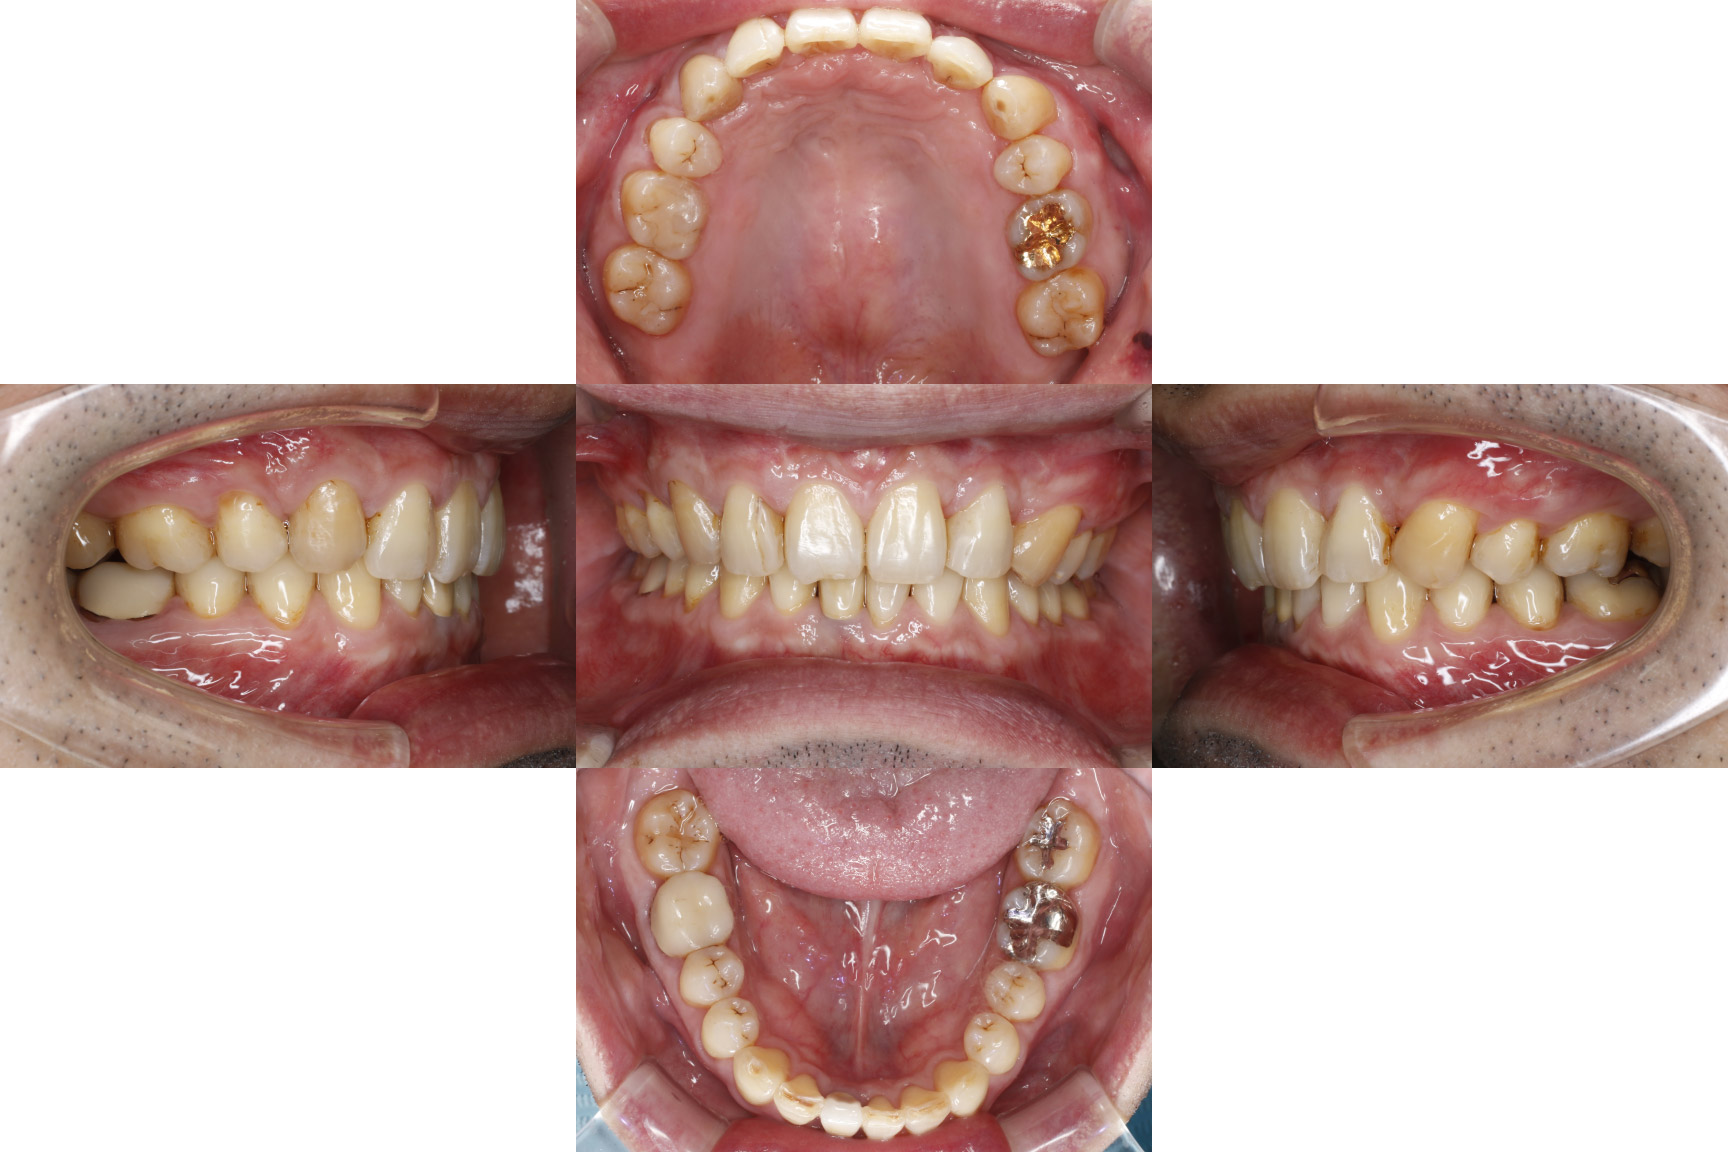

当院の症例

| 主訴 | 【主訴】ディープバイト,すきっ歯 【診断・症状】左上C残存、下顎右下1番欠損、上顎前突、空隙歯列、過蓋咬合 |

| 抜歯 | 有(左上c、上の4,4) |

| 矯正の装置 | 裏側矯正(舌側矯正) |